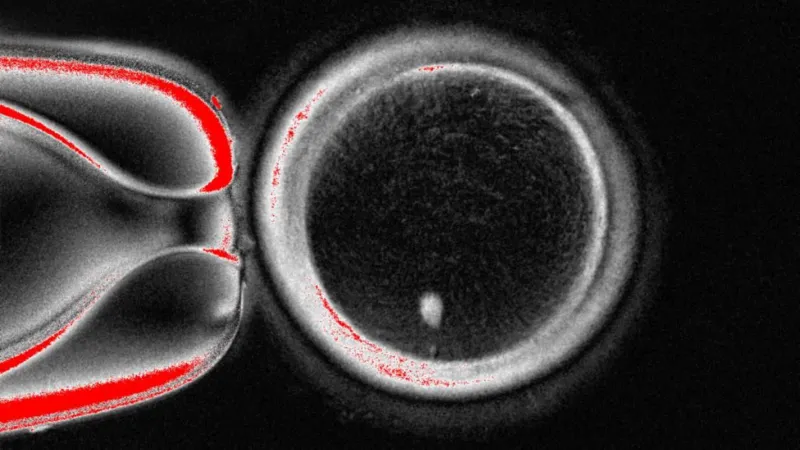

अमेरिकी वैज्ञानिकहरूले पहिलो पटक मानव छालाको कोशिकाबाट डीएनए परिवर्तन गरेर प्रारम्भिक चरणको मानव भ्रूण बनाएका छन् र त्यसलाई शुक्रकीटद्वारा निषेचन गरेका छन्।यो प्रविधिले बुढ्यौली वा रोगका कारण हुने बाँझोपनलाई समाधान गर्न सक्छ, किनभने शरीरको लगभग कुनै पनि कोशिकालाई जीवनको सुरुवातको बिन्दुको रूपमा प्रयोग गर्न सकिन्छ।यसले समलिङ्गी जोडीहरूलाई पनि उनीहरूको आनुवंशिक रूपमा सम्बन्धित सन्तान जन्माउन सम्भव बनाउन सक्छ।तर, यो प्रविधिलाई पूर्ण बनाउन अझै धेरै सुधार आवश्यक छ, जसमा एक दशक लाग्न सक्छ, र त्यसपछि मात्र प्रजनन क्लिनिकहरूले यसलाई प्रयोग गर्ने विचार गर्न सक्छन्।विज्ञहरूले यो एक प्रभावशाली उपलब्धि भएको बताएका छन्, तर यसले सम्भव बनाएको कुराहरूबारे जनतासँग खुला छलफल आवश्यक रहेको उल्लेख गरेका छन्।पहिले प्रजननको कथा सरल थियो: पुरुषको शुक्रकीट र महिलाको अण्डाणु एक आपसमा मिलेर भ्रूण बनाउँथे, र नौ महिनापछि बच्चा जन्मिन्थ्यो।तर अब वैज्ञानिकहरूले यो नियम परिवर्तन गर्दैछन्। यो नयाँ प्रयोग मानव छालाबाट सुरु हुन्छ।ओरेगन स्वास्थ्य र विज्ञान विश्वविद्यालय (OHSU) को अनुसन्धान टोलीले छालाको कोशिकाबाट नाभिक (न्यूक्लियस) निकालेर यो प्रक्रिया सुरु गरेको छ। नाभिकमा शरीर बनाउन आवश्यक सम्पूर्ण आनुवंशिक कोडको एक प्रति हुन्छ।यो नाभिकलाई दान गरिएको अण्डाणुमा राखिन्छ, जसको आनुवंशिक जानकारी पहिले नै हटाइएको हुन्छ।यो प्रक्रिया १९९६ मा विश्वको पहिलो क्लोन गरिएको स्तनधारी जीव डल्ली भेडा बनाउने प्रविधिसँग मिल्दोजुल्दो छ।तर, यो अण्डाणु शुक्रकीटद्वारा निषेचनको लागि तयार हुँदैन, किनभने यसमा पहिले नै ४६ वटा क्रोमोसोमको पूर्ण सेट हुन्छ।मानव शरीरमा २३ जोडी क्रोमोसोम हुन्छन्, जुन आमा र बाबुबाट आधा-आधा प्राप्त हुन्छन्। यो अण्डाणुमा यी सबै क्रोमोसोम पहिलेदेखि नै हुन्छन्।त्यसैले, अर्को चरणमा अण्डाणुलाई आधा क्रोमोसोम हटाउन प्रेरित गरिन्छ, जसलाई अनुसन्धानकर्ताहरूले "माइटोमियोसिस" (माइटोसिस र मियोसिसको संयोजन) भनेका छन्।नेचर कम्युनिकेशन्स जर्नलमा प्रकाशित यो अध्ययनले ८२ वटा कार्यात्मक अण्डाणु बनाइएको देखाएको छ। यी अण्डाणुहरूलाई शुक्रकीटद्वारा निषेचन गरिएको थियो र केही भ्रूणहरू छ दिनसम्मको प्रारम्भिक चरणमा विकसित भए।"हामीले असम्भव ठानिएको कुरा हासिल गर्‍यौं," ओरेगन स्वास्थ्य र विज्ञान विश्वविद्यालयको भ्रूण कोशिका र जीन थेरापी केन्द्रका निर्देशक प्रोफेसर शौखरत मितालिपोभले भने।तर यो प्रविधि अझै पूर्ण छैन। अण्डाणुले कुन क्रोमोसोम हटाउने भनेर अनियमित रूपमा छनोट गर्छ, जसले गर्दा रोगबाट बच्न २३ प्रकारका क्रोमोसोम मध्ये प्रत्येकको एक-एक प्रति हुनुपर्नेमा केहीको दुई प्रति र केहीको शून्य प्रति हुन्छ।सफलताको दर पनि कम छ (लगभग ९%) र क्रोमोसोमहरूले डीएनए पुनर्व्यवस्था गर्ने महत्त्वपूर्ण प्रक्रिया, जसलाई "क्रसिङ ओभर" भनिन्छ, त्यो पनि छुट्छ।प्रोफेसर मितालिपोभले भने, "हामीले यो प्रविधिलाई पूर्ण बनाउनुपर्छ। अन्ततः, मलाई लाग्छ भविष्य यही दिशामा अघि बढ्नेछ, किनभने धेरै बिरामीहरू छन् जो सन्तान जन्माउन सक्दैनन्।"यो प्रविधि इन भिट्रो गेमेटोजेनेसिस (IVG) को क्षेत्रको हिस्सा हो, जसले शरीरबाहिर शुक्रकीट र अण्डाणु बनाउने लक्ष्य राख्छ।यो प्रविधि अहिले पनि वैज्ञानिक खोजको चरणमा छ, तर यसको दृष्टिकोण भनेको IVF (इन भिट्रो फर्टिलाइजेशन) बाट लाभ लिन नसक्ने जोडीहरूलाई मद्दत गर्नु हो, जस्तै पर्याप्त शुक्रकीट वा अण्डाणु नहुनेहरू।यसले बुढ्यौलीका कारण अण्डाणु नहुने महिलाहरू, पर्याप्त शुक्रकीट उत्पादन नगर्ने पुरुषहरू, वा क्यान्सरको उपचारले बाँझोपन भएका व्यक्तिहरूलाई सहयोग गर्न सक्छ।यो प्रविधिले प्रजननका नियमहरूलाई पुनर्लेखन गर्छ। आज वर्णन गरिएको प्रविधिमा महिलाको छाला कोशिका प्रयोग गर्नुपर्दैन, पुरुषको पनि प्रयोग गर्न सकिन्छ।यसले समलिङ्गी जोडीहरूलाई उनीहरू दुवैसँग आनुवंशिक रूपमा सम्बन्धित सन्तान जन्माउने सम्भावना खोल्छ। उदाहरणका लागि, समलिङ्गी पुरुष जोडीमा, एक पुरुषको छालाबाट अण्डाणु बनाउन सकिन्छ र अर्को पुरुषको शुक्रकीटले त्यसलाई निषेचन गर्न सकिन्छ।"यो विधिले अण्डाणु वा शुक्रकीटको कमीका कारण बाँझोपन भएका लाखौं मानिसहरूलाई आशा दिनुका साथै समलिङ्गी जोडीहरूलाई दुवैसँग आनुवंशिक रूपमा सम्बन्धित सन्तान जन्माउने सम्भावना प्रदान गर्छ," ओरेगन स्वास्थ्य र विज्ञान विश्वविद्यालयकी प्रोफेसर पाउला अमातोले भनिन्।हल विश्वविद्यालयका प्रजनन चिकित्सा प्राध्यापक रोजर स्टर्मीले यो विज्ञान "महत्त्वपूर्ण" र "प्रभावशाली" भएको बताए।उनले थपे, "यस्ता अनुसन्धानले प्रजनन अनुसन्धानमा नयाँ प्रगतिहरूबारे जनतासँग निरन्तर खुला संवादको महत्त्वलाई जोड दिन्छ। यस्ता सफलताहरूले बलियो शासन र जवाफदेहिताको आवश्यकता देखाउँछन्, जसले जनताको विश्वास निर्माण गर्छ।"एडिनबर्ग विश्वविद्यालयको MRC सेन्टर फर रिप्रोडक्टिभ हेल्थका उपनिर्देशक प्रोफेसर रिचर्ड एन्डरसनले नयाँ अण्डाणु बनाउने क्षमताले "महत्त्वपूर्ण प्रगति" ल्याउने बताए।उनले भने, "यसमा धेरै महत्त्वपूर्ण सुरक्षा चिन्ताहरू छन्, तर यो अध्ययनले धेरै महिलाहरूलाई उनीहरूको आनुवंशिक सन्तान जन्माउने सहयोग गर्ने दिशामा एक कदम हो।"